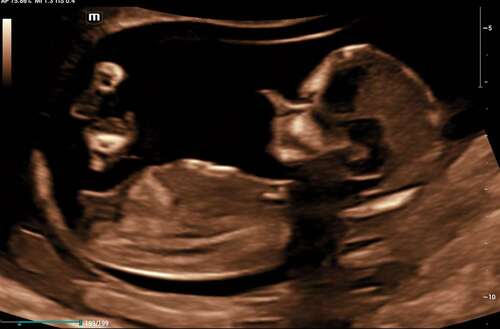

Hoihoi, dit heb ik laten doen, gewoon uit nieuwsgierigheid. Ik heb nog een foto, kan iemand zien of dit een beetje klopt ?

Hoihoi, dit heb ik laten doen, gewoon uit nieuwsgierigheid. Ik heb nog een ...

Deze